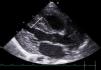

Los controles ecocardiográficos reglados mostraron normalización de la función sistólica biventricular y mejoría estructural, aunque persistía un ventrículo izquierdo engrosado y ventrículo derecho trabeculado (fig. 1).

Figura 1.

Ecocardiografía en plano paraesternal largo en la que se objetiva engrosamiento del tabique interventricular (5,5mm).